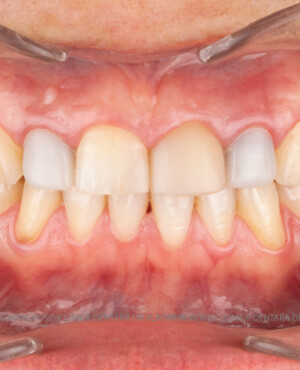

Transformările estetice și impactul reabilitării asupra vieții pacienților

Reabilitarea dentară produce o schimbare vizibilă și profundă în aspectul pacientului, cu efecte pozitive evidente asupra stimei de sine și a calității vieții. Mulți pacienți relatează bucuria redobândirii funcției masticatorii și dispariția complexelor legate de aspectul dentar.